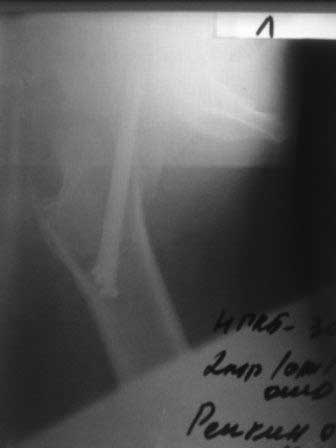

[Ortho] Ложный сустав шейки бедра

Обратился б-ной около 40 лет, три месяца назад оперирован в г.Алмате. При осмотре ходит с двумя костылями, беспокоят постоянные боли, симптом прилипшей пятки положительный, посмотрел под Р-скопией; сращения нет.

P.S.   Р-снимки сразу после операции,  и вчерашные.

Имя     : 1.jpg